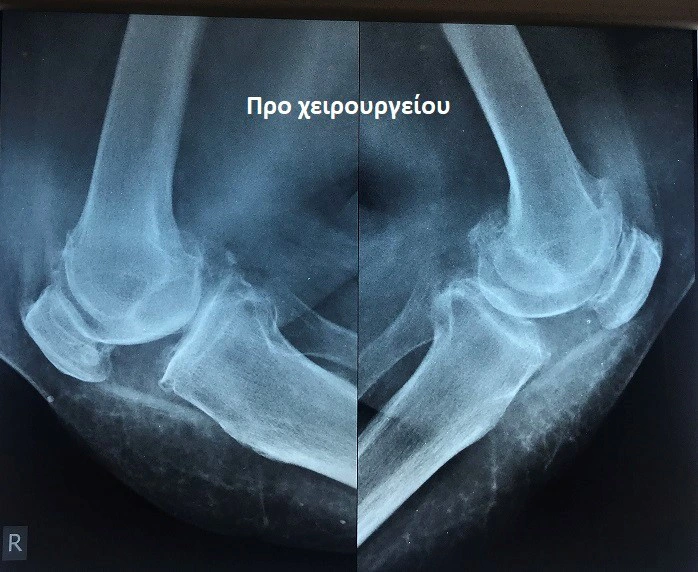

Από το προσωπικό αρχείο του ιατρού